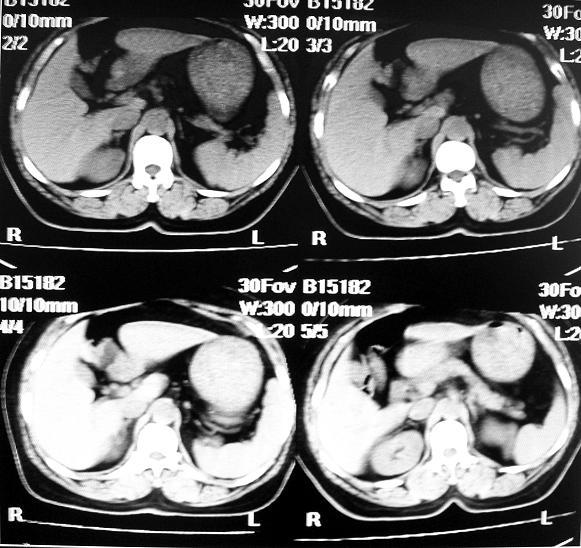

标题: CT10687:肾脏CT,请会诊

女,53岁,尿频尿急来诊,其他层面无异常未上传。

肾柱肥大可能?请增强结合b超

像是一个正常的驼峰样改变!!不放心就做个增强

应该是正常的表现!左肾上极外侧变异较多;建议增强!

正常!日常检查中多有肾驼峰状改变,为正常变异